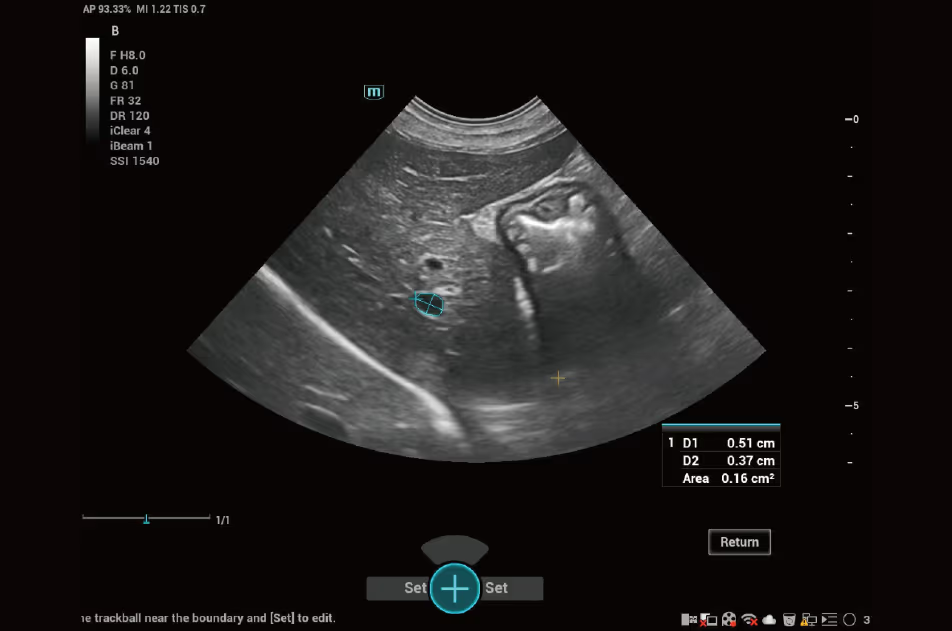

Tek bir tuşa basarak lezyonun sınırını çevreleyebilir ve hassas ölçüm alabilirsiniz.